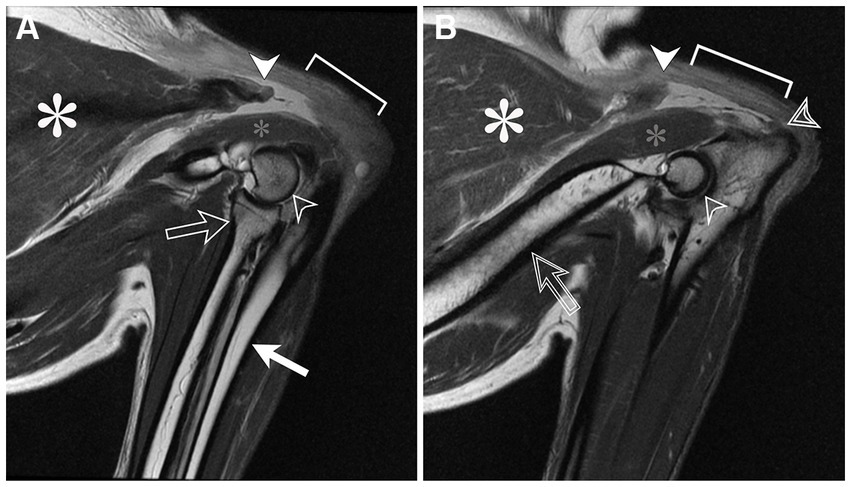

Bajo anestesia general, la resonancia magnética de los codos se realizó utilizando la misma unidad de resonancia magnética y la bobina de columna vertebral phased array. Los codos se colocaron en flexión. Se obtuvieron T1W sagitales y transversales, T2W utilizando supresión de grasa por desplazamiento químico e imágenes ponderadas por densidad de protones (PD) de ambos codos. Ambos tendones del tríceps braquial de inserción estaban completamente avulsionados distal a la unión musculotendinosa (Figuras 1, 2). En el lado derecho, había retracción proximal del músculo tríceps y ondulación del tendón remanente. Distal a la avulsión, un segmento de tendón de 0,7 cm de largo permaneció unido al tubérculo olécranon. En el lado izquierdo, un segmento de tendón de 1,7 cm de largo permanecía unido al tubérculo del olécranon con un menor espacio de retracción entre el músculo y el tendón. En ambos segmentos tendinosos remanentes, hubo un aumento lineal de la señal de T2W y DP compatible con desgarro fibrilar intrasustancia. Hebras delgadas y filamentosas de fibras tendinosas proyectadas desde ambos extremos de los segmentos tendinosos. En ambos músculos tríceps braquial, hubo un aumento de la señal T2W dentro de la cabeza accesoria y la fascia adyacente y un aumento de la señal T2W y PD que rodea la inserción del tendón del tríceps consistente con edema. La otra cabeza de los músculos tríceps braquial no se vio afectada. El resto de los tejidos blandos periarticulares eran normales. Ambos codos carecían de cambios degenerativos o derrame articular.

Los hallazgos de la resonancia magnética fueron consistentes con una avulsión completa del tendón del tríceps braquial derecho cerca de la inserción del olécranon y una avulsión completa del tendón del tríceps braquial izquierdo en la porción media del tendón.